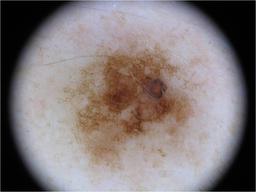

{

"age_approx": 55,

"anatom_site_general": "anterior torso",

"concomitant_biopsy": false,

"diagnosis_1": "Benign",

"diagnosis_2": "Benign melanocytic proliferations",

"diagnosis_3": "Nevus",

"diagnosis_4": "Nevus, Atypical, Dysplastic, or Clark",

"diagnosis_5": "Nevus, Dysplastic",

"image_type": "dermoscopic",

"melanocytic": true,

"sex": "female"